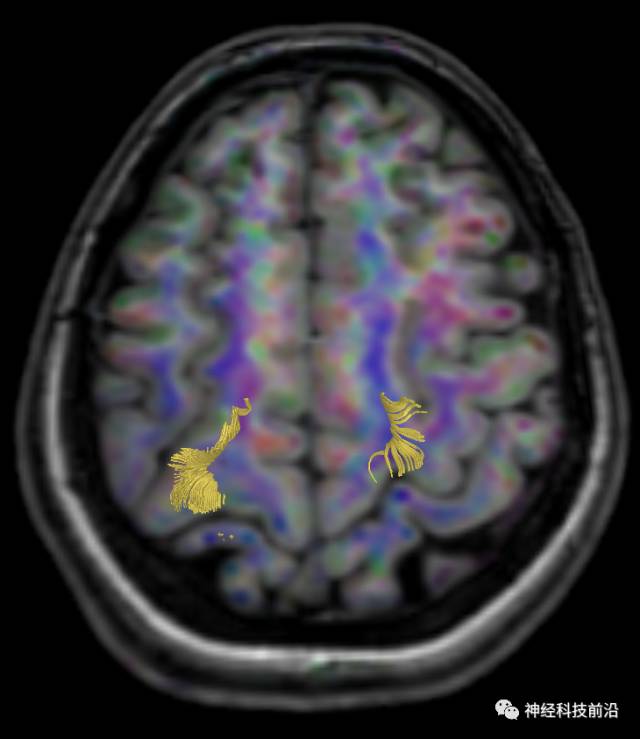

DTI原始图像与T1融合图像

皮质脑桥束与脑干高信号(黄色)纤维束

皮质脊髓束与皮质脑桥束的关系毗邻